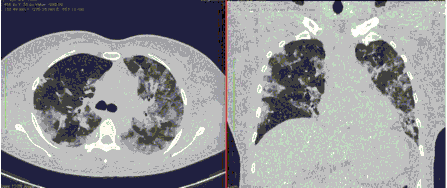

4.3. ЛУЧЕВАЯ ДИАГНОСТИКА COVID-19

Методы лучевой диагностики применяют для выявления COVID-19 пневмоний, их осложнений, дифференциальной диагностики с другими заболеваниями легких, а также для определения степени выраженности и динамики изменений, оценки эффективности проводимой терапии.

К методам лучевой диагностики патологии ОГК пациентов с предполагаемой/установленной COVID-19 пневмонией относят:

- Компьютерную томографию легких (КТ),

КТ имеет высокую чувствительность в выявлении изменений в легких, характерных для COVID-19. Применение КТ целесообразно для первичной оценки состояния ОГК у пациентов с тяжелыми прогрессирующими формами заболевания, а также для дифференциальной диагностики выявленных изменений и оценки динамики процесса. КТ позволяет выявить характерные изменения в легких у пациентов с COVID-19 еще до появления положительных лабораторных тестов на инфекцию с помощью МАНК. В то же время, КТ выявляет изменения легких у значительного числа пациентов с бессимптомной и легкой формами заболевания, которым не требуется госпитализация. Результаты КТ в этих случаях не влияют на тактику лечения и прогноз заболевания при наличии лабораторного подтверждения COVID-19. Поэтому массовое применение КТ для скрининга асимптомных и легких форм болезни не рекомендуется. При первичном обращении пациента с подозрением на COVID-19 рекомендуется назначать КТ только при наличии клинических и инструментальных признаков дыхательной недостаточности (SpO2 < 95%, ЧДД > 22).

3. Применение лучевых методов у пациентов с симптомами ОРВИ легкой степени тяжести и стабильном состоянии пациента, возможно только по конкретным клиническим показаниям, в том числе при наличии факторов риска, при условии достаточных технических и организационных возможностей. Методом выбора в этом случае является КТ легких по стандартному протоколу без внутривенного контрастирования или РГ при ограниченной доступности КТ. Использование УЗИ в этих случаях нецелесообразно. Применение КТ исследования в сроки ранее 3 - 5 дней с момента появления симптомов заболевания, а также при отсутствии клинических проявлений поражения бронхолегочной системы является нецелесообразным. Выполнение КТ целесообразно при наличии клинических и инструментальных признаков дыхательной недостаточности (SpO2 < 95%, ЧДД > 22), либо при дифференциальной диагностике с другим заболеванием.